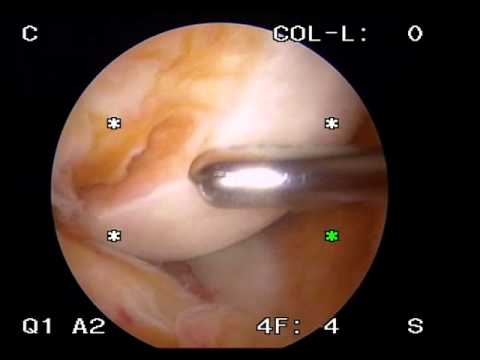

Hip arthroscopy for PVNS posterior peripheral portals.mpeg :

Pigmented Villonodular Synovitis Surgery by Dr HC Chang.wmv :